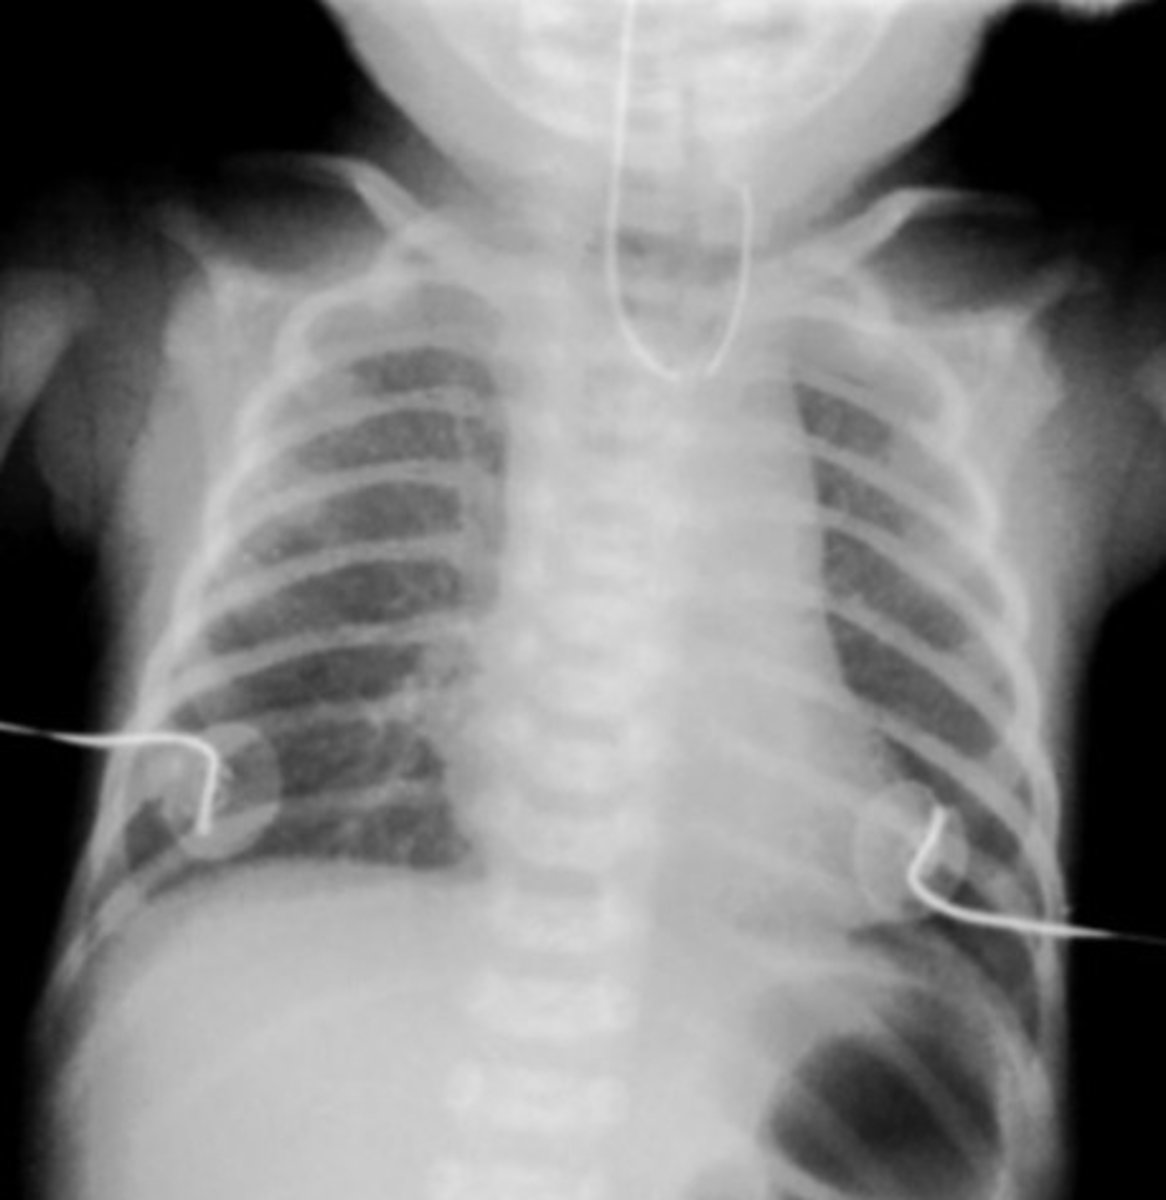

What is a congenital diaphragmatic hernia (CDH), & what is the primary complication of this condition?

Failure of diaphragmatic tissue to close resulting in the abdominal contents to herniate into the thoracic cavity; respiratory insufficiency (herniated intestines interfere w/ lung development)

What are some s/sxs of a CDH?

Respiratory distress, scaphoid abdomen, shift of heart sounds to the right, tachypnea, nasal flaring, cyanosis, bowel sounds or absent breath sounds on affected side

What is the best initial test for a CDH? How is it managed?

Diagnosis: CXR

Treatment: intubation & mechanical ventilation, surgery after 24-48 hrs (delayed to allow for improvement in pulmonary HTN)